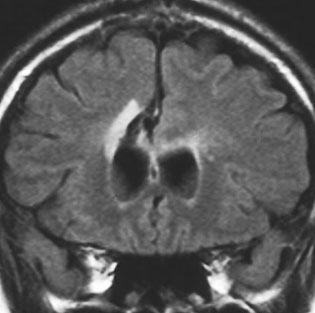

フレア画像です。左上前頭回の星細胞腫ですが,境界がとてもはっきりしていて限局性 localized single gyrus glioma です。びまん性 diffuseには見えません。IDH1の変異があり,1p/19qの欠失はないので星細胞腫グレード2です。上の例とは全く違う臨床像を示しますが,分子病理でも区別はつきません。頑張って早めに全摘出して治してしまった方がいいタイプです。再発を避けるために,supratotal resectionと言って,周囲の正常脳組織も10mmくらい余分に摘出します。